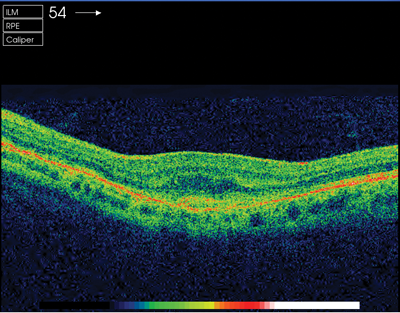

After treatment her vision improved by four lines on logmar, the sub-retinal fluid was resolving bilaterally, and there was evidence of sub-retinal fibrosis in the left eye. Changes in optical coherence tomography (OCT) and FFA are demonstrated in Figures 2-5.

Figure 4: OCT pre-injection.